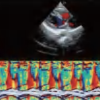

DW-L50 Exp

DW-L50 Exp

Aparato de Diagnóstico Ultrasónico Digital a Color Completo de Tipo Laptop

El DW-L50 Exp, impulsado por la avanzada plataforma de ultrasonido ST-U, ofrece imágenes ultra claras en todo momento. Con una movilidad y adaptabilidad sobresalientes, funciona de manera fiable en diversos entornos clínicos complejos. Su introducción permite que más instituciones médicas accedan a tecnología de ultrasonido rentable y de alto rendimiento.